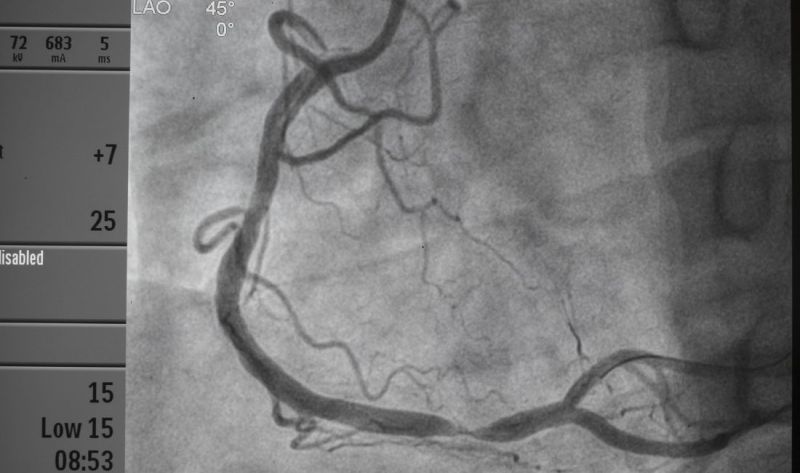

• CT angiografija: Pruža visokokvalitetne slike koje pomažu u identifikaciji stenoze.

Ove dijagnostičke metode omogućavaju lekarima da precizno utvrde prisustvo i stepen stenoze plućne arterije.